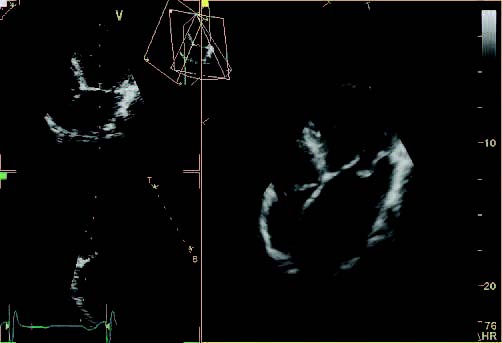

- B-Mode

- Dual screen